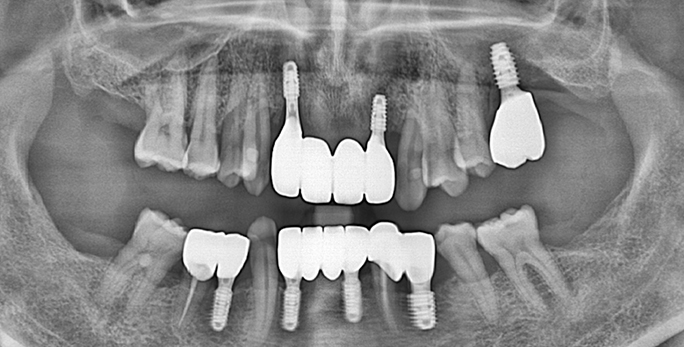

• 전체치아 10개 이상 임플란트